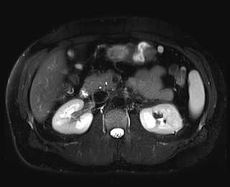

Magnetická rezonance (též MR, MRI, z anglického "magnetic resonance imaging") je zobrazovací technika používaná především ve zdravotnictví k zobrazení vnitřních orgánů lidského těla. S pomocí MRI je možné získat řezy určité oblasti těla, ty dále zpracovávat a spojovat až třeba k výslednému 3D obrazu požadovaného orgánu. Magnetická rezonance využívá velké magnetické pole a elektromagnetické vlnění s vysokou frekvencí. Nenese tedy žádná rizika způsobená zářením. Podstatou barevného odlišení jednotlivých tkání je jejich rozdílné chování při stejném vnějším působení. Jako synonymum bývá někdy používáno výrazu jaderná tomografie, od něho je ale upouštěno, protože mylně vzbuzuje dojem jakési souvislosti s jadernou energií. Více používaná zkratka MRI pochází z anglického sousloví Magnetic Resonance Imaging. Další rozvoj této metody vedl v poslední době k vývoji funkční magnetické rezonance (fMRI) a DTI = DT-MRI. Přístroj magnetické rezonance obsluhuje radiologický asistent.

Na základě naměřeného indukovaného napětí a dalších parametrů je signál pomocí složitých procesů a algoritmů převeden na škálu šedé. Právě kvůli tomu, že výsledný signál závisí na mnoha parametrech, nedá se použít žádné stupnice, která by přesně určila jednotlivé tkáně, proto se k interpretaci obrazů používá spíše rozhraní, na kterých se mění intensita signálu.

Výhodou MRI vůči ostatním zobrazovacím metodám v diagnostické radiologii je větší přesnost při zobrazení většiny orgánů, jež je důsledkem rozdílné intenzity signálu u odlišných měkkých tkání. Navíc toto zobrazení probíhá bez možného škodlivého ionisujícího záření. Některé orgány jako nervy či mozková tkáň bylo možné neinvazivně zobrazovat až právě pomocí MRI. Díky rozsahu nastavení vyšetření je možné dosáhnout rozlišení, které dalece přesahuje možnosti rentgenu či CT. Dalšího zlepšení může být ještě dosaženo podáním kontrastní látky, která pomůže odhalit přítomnost zánětů nebo nádorových tkání. Nový vývoj umožnil zkrátit časový interval získání jednoho snímku na několik milisekund. To umožnilo tzv. MRI-Fluoroskopii, při které jsou pohybující se orgány zobrazovány v reálném čase, což nachází široké uplatnění v intervenční radiologii.